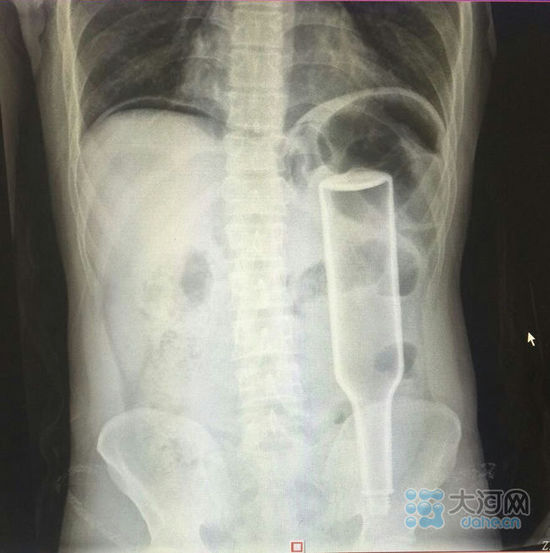

看这片子,花露水瓶子已经很“深入”了。

大河网讯在郑州务工的外地男子王某,下班到家后闲着没事儿干,于是将一个长18厘米的花露水瓶子塞进了自己的肛门,不过因为用力过猛,快感没来,瓶子却把直肠给戳破了,疼得受不了了,王某羞答答地来到郑州人民医院就诊,医生给他做了手术,现在已经出院。